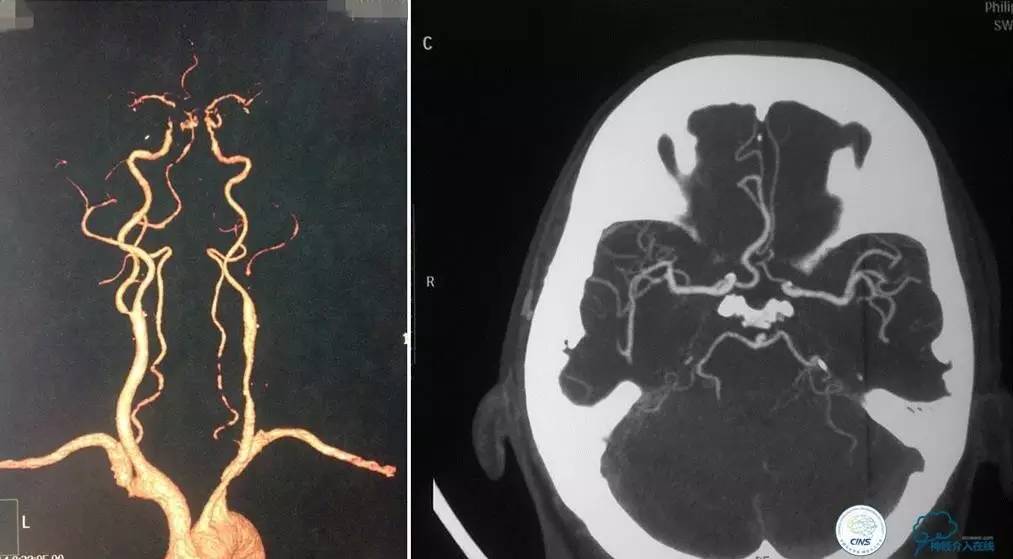

▼影像学资料

入院后,患者症状稍有加重,出现走路不稳,查体发现两手指鼻不稳。行颅脑MRI检查。给予双抗血小板、调脂、改善脑循环、营养神经等药物治疗。立普妥20mg qn。实验室检查:LDL-C:3.31mmol/L。

▼颅脑CT灌注扫描

▼2014-12-08

▼Apollo 3.0*13mm